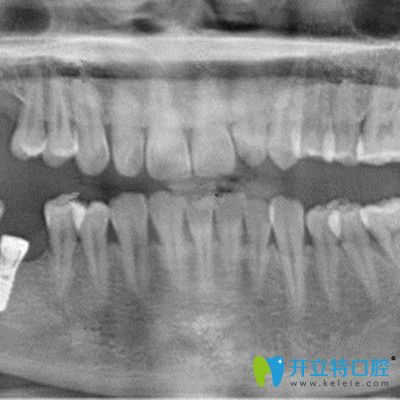

再次到,谭医生表示我的牙骨质条件还是挺好的,当天就做了手术,装入了种植体,戴了临时冠,整个手术过程大概持续了一个小时左右。因为做的是微创即可种植技术,所以基本没有痛感。

手术有3个月了,今天过来复诊,谭医生告知检查结果显示我的牙槽骨愈合的较好,当天就更我装了种植牙的牙冠,现在我感觉跟真牙基本没有区别,吃东西也完全不受影响了。